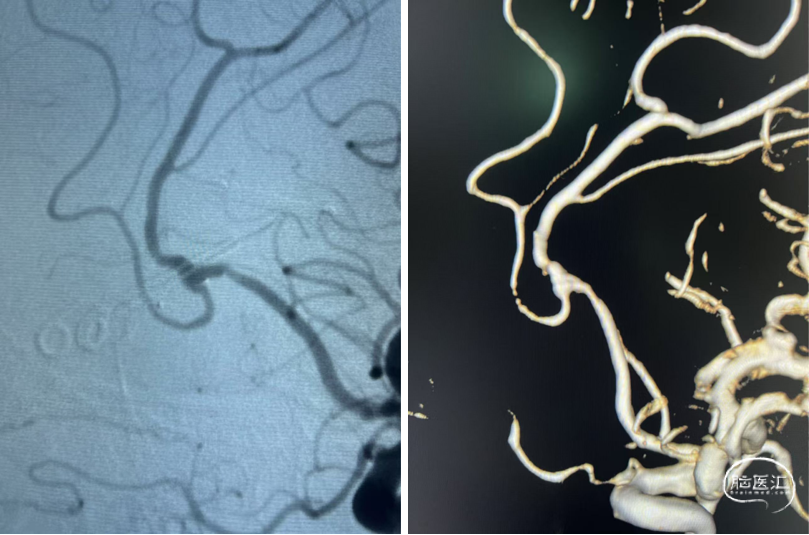

DSA

平均宽度(4.5+3.8)=4.2mm,最小深度7.5mm,选择SL5x3